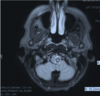

A patient presents with a one-year history of intermittent twitching of the right side of the face. During surgery to address the twitching, the nerve indicated by the arrow in the image shown is injured. This injury will most likely cause which of the following neurological deficits?

A. Unilateral Facial Numbness B. Vertigo

C. Dysphagia

D. Sensorineural hearing loss

E. Unilateral Facial Weakness

Correct Answer: Dysphagia